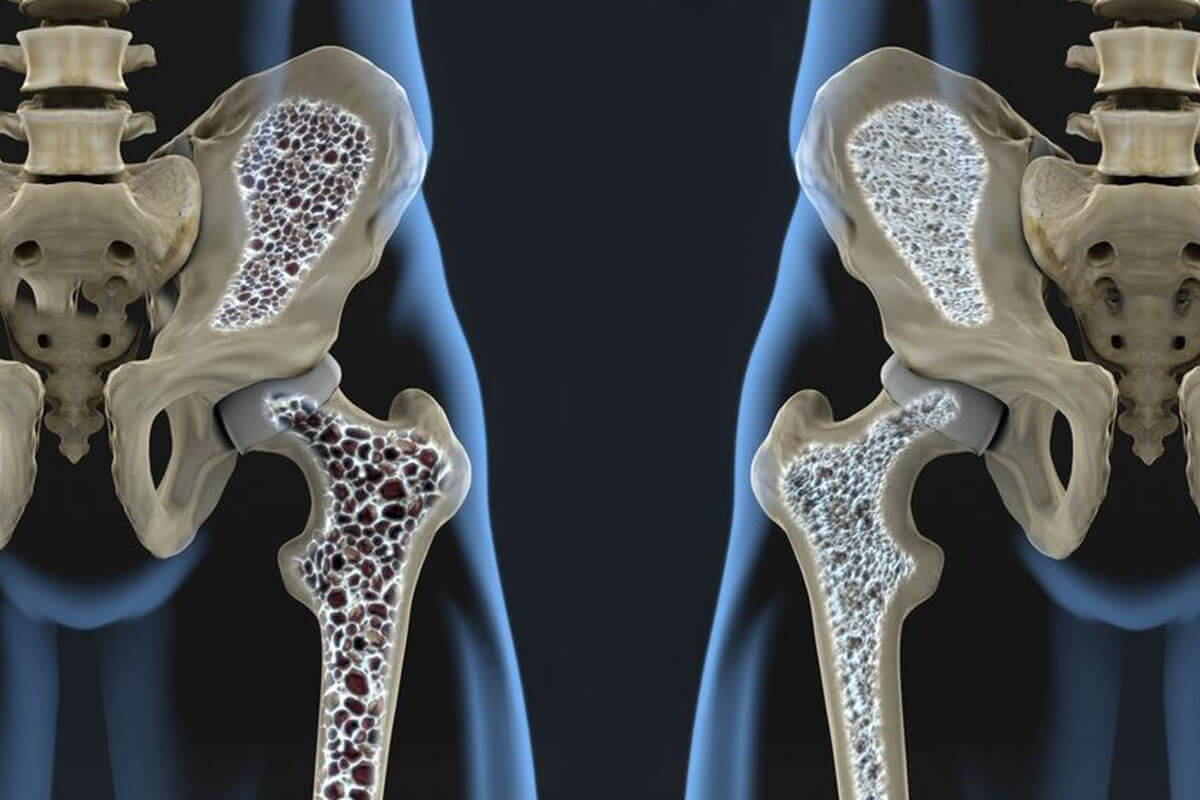

The bone is a living tissue, and as such it is constantly being broken down to create new bone. However, when the rebuilding process is slower than the breaking down process, the bones become fragile and brittle. This is what happens when you develop osteoporosis. Osteoporosis is more common in women than men, and affects about 200 million women all over the world. Even though this disorder affects women of all age and races, it is more common in older white and Asian women.

The fractures that are associated with osteoporosis usually occur in your spine, hip, and wrist. The bones become so brittle that even everyday activities like bending over or stepping on to the pavement can result in fractures. Early stages of osteoporosis do not show any symptoms, but when it reaches an advanced stage, symptoms like loss of height, back pain, neck pain, fractures, and stooping posture can be seen. A simple bone density test that shows the extent of osteoporosis bone loss is used when you want to diagnose this disorder.